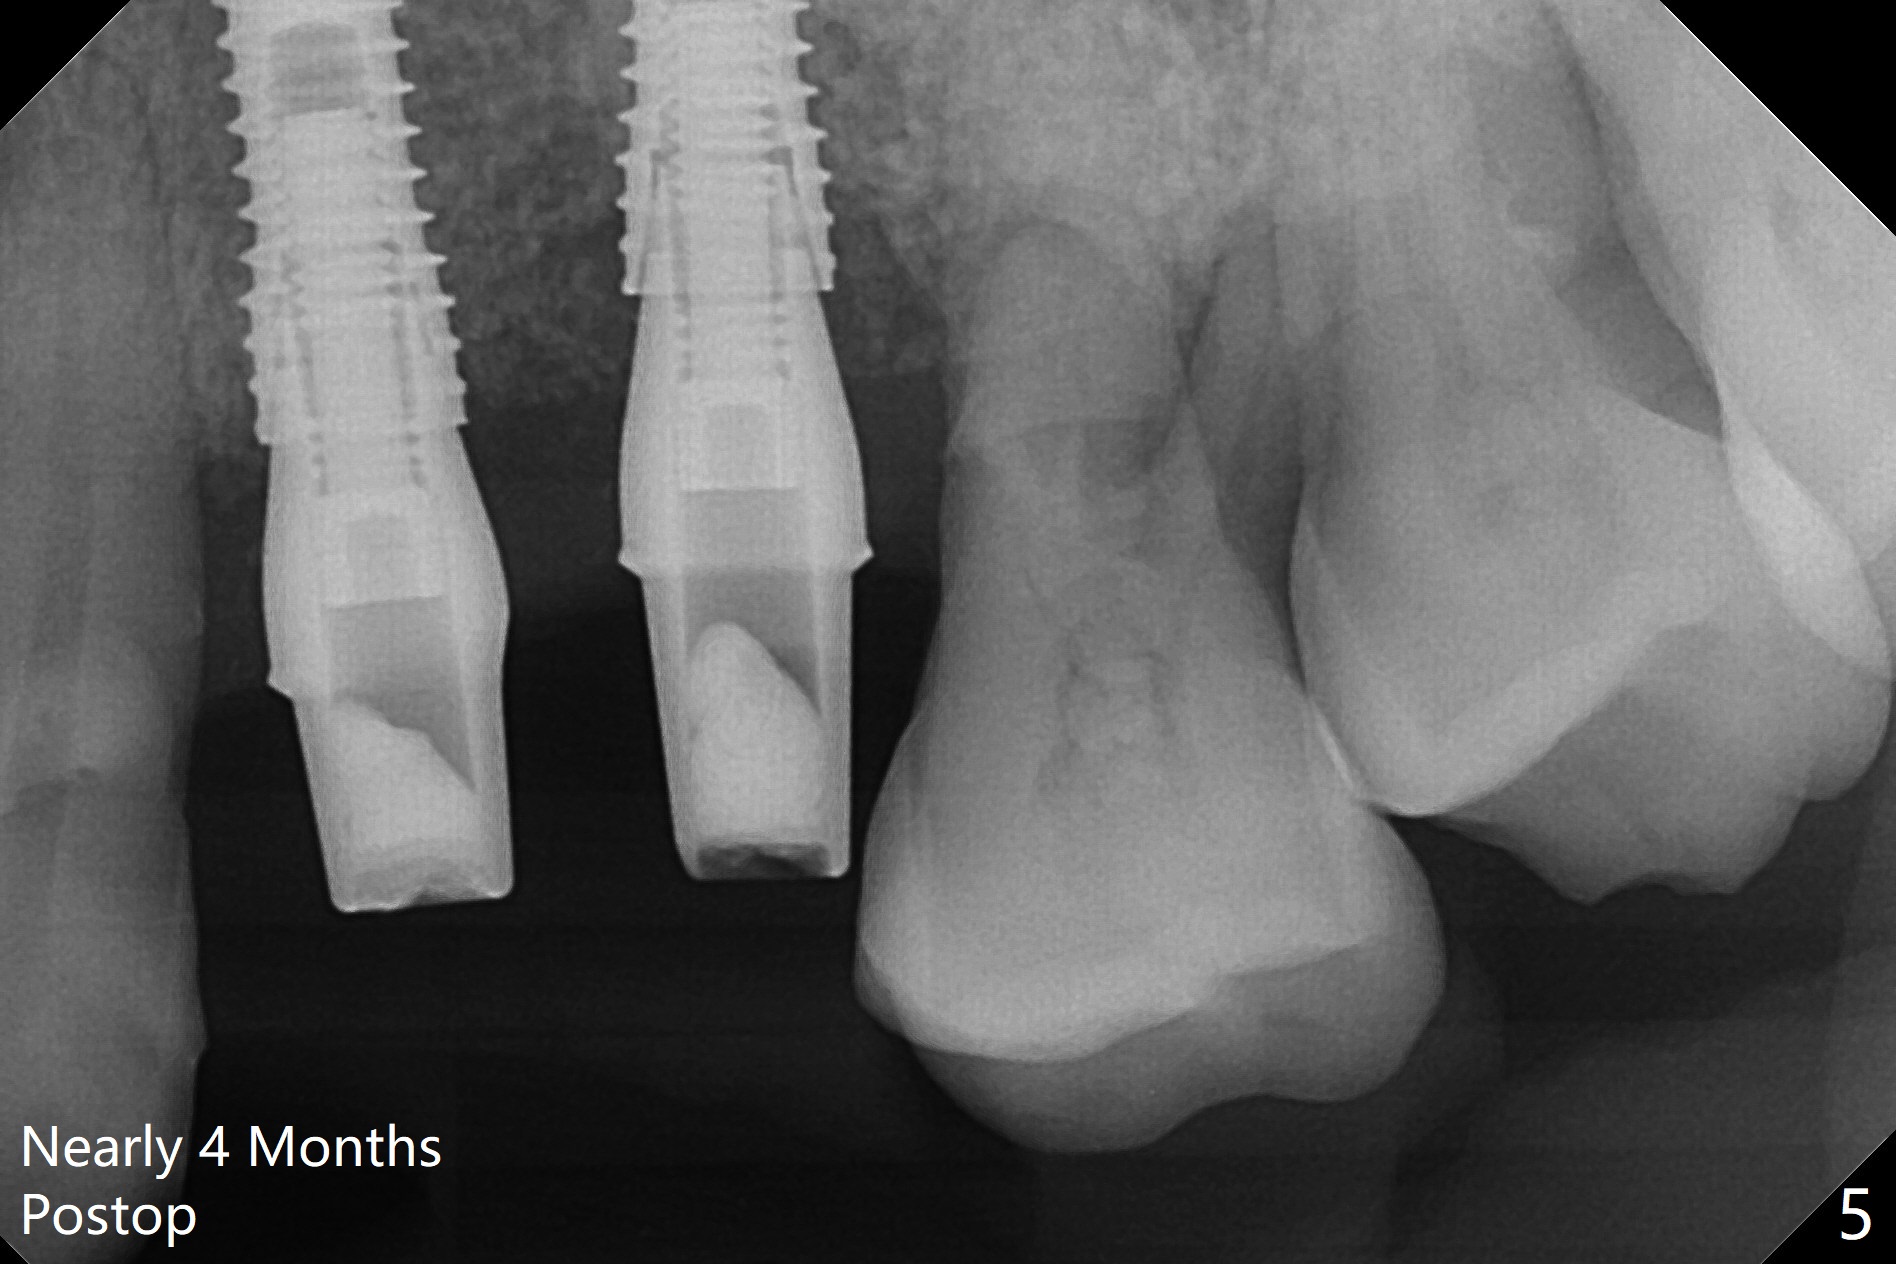

A 66-year-old woman returns to office requesting implant placement at #12 and 13 at an appointment supposed for #5 impression. Depth of osteotomy is 20 mm (gingival level, Fig.1 ( 2mm)). After correction of trajectory at #12 and 3 mm drill for 16 mm at the sites, two of 3.8x16 mm implant are placed with insertion torques of 35 and 15 Ncm, respectively (Fig.2). Before and after change into shorter abutments (4.5x4(4) and (5)), Vera Graft is placed (Fig.3 *). To increase stability, either increase the diameter (4 (Fig.4 at #5) or 4.5 mm instead of 3.8) or length of the implants (red dashed line: sinus floor). Or use dummy implants. The allograft appears to have been incorporated into the host bone nearly 4 months postop (Fig.5). The abutment of the isolate implant at #5 becomes loose twice (Fig.4). To reduce the chance of abutment loosening at #12 and 13, can you make splinted crowns? If the two separate crowns have been fabricated, can you make a slot (with light undercut) in the proximal area of each crown (Fig.6 (occlusal view): S) in addition to access hole (A)? After cementation, composite will be placed in the slots (lock) so that the crowns will not rotate and become loose.